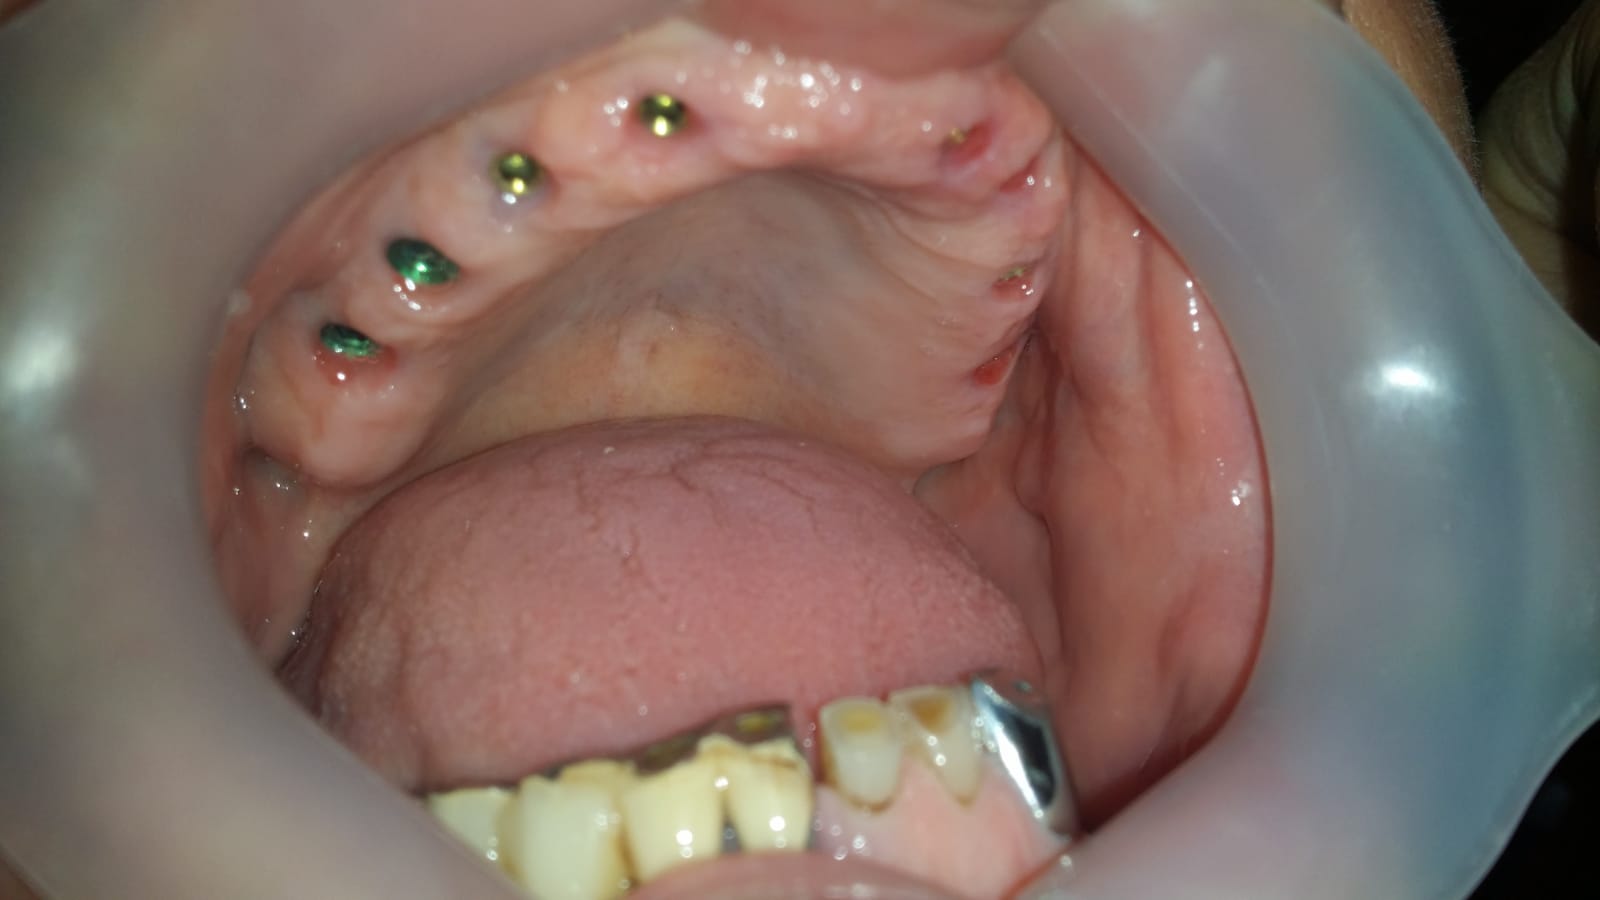

Reabilitare mandibulara pe sistem Fast and Fixed in 24 ore

Reabilitare pe implanturi dentare